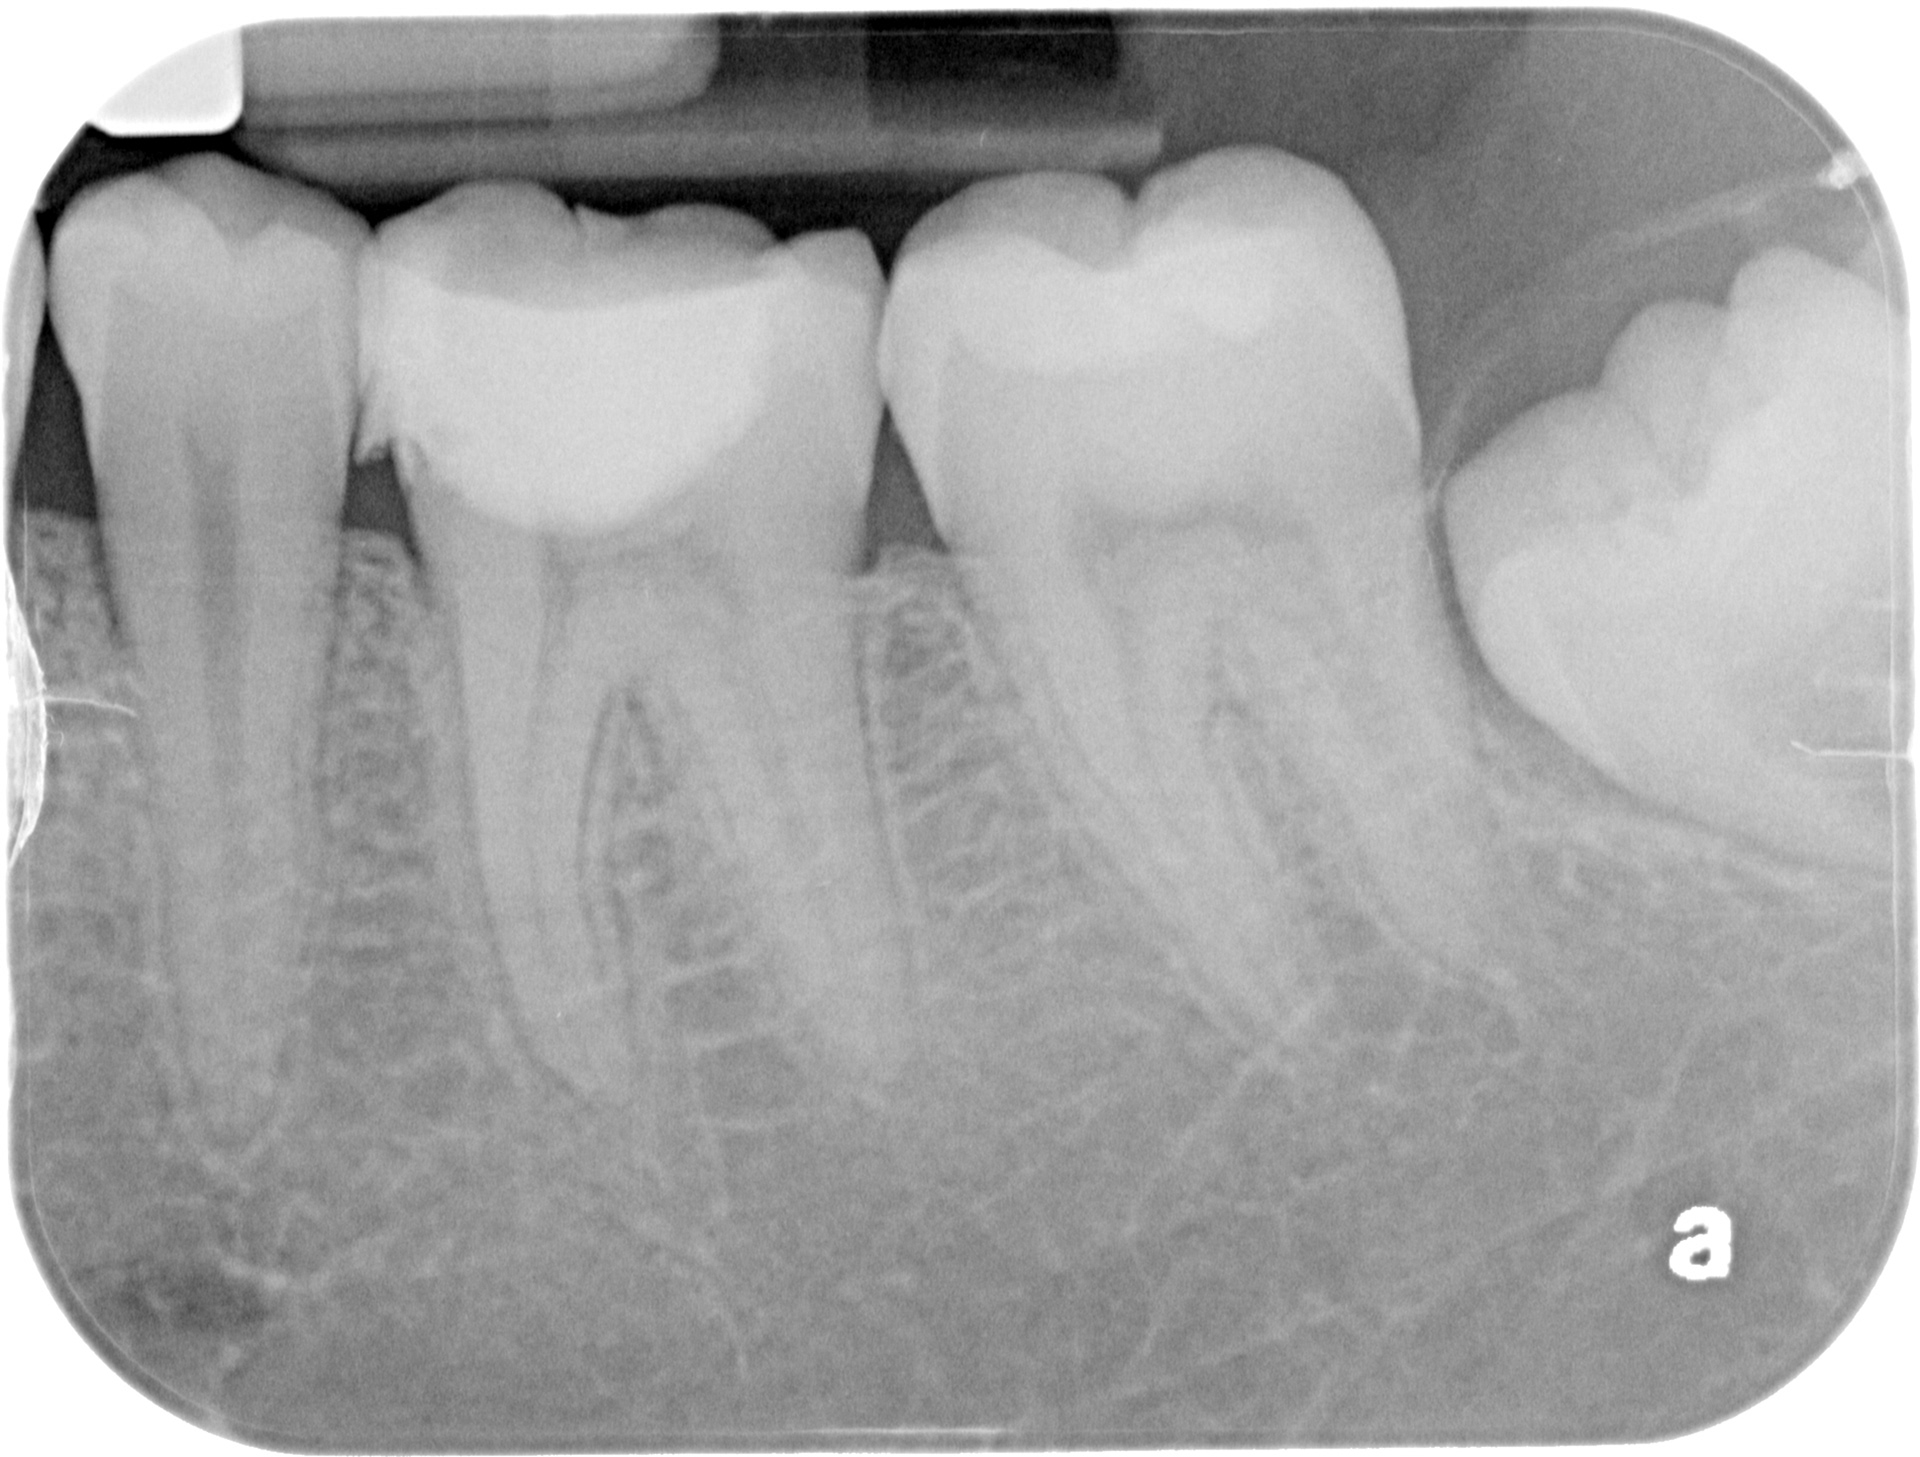

Initial